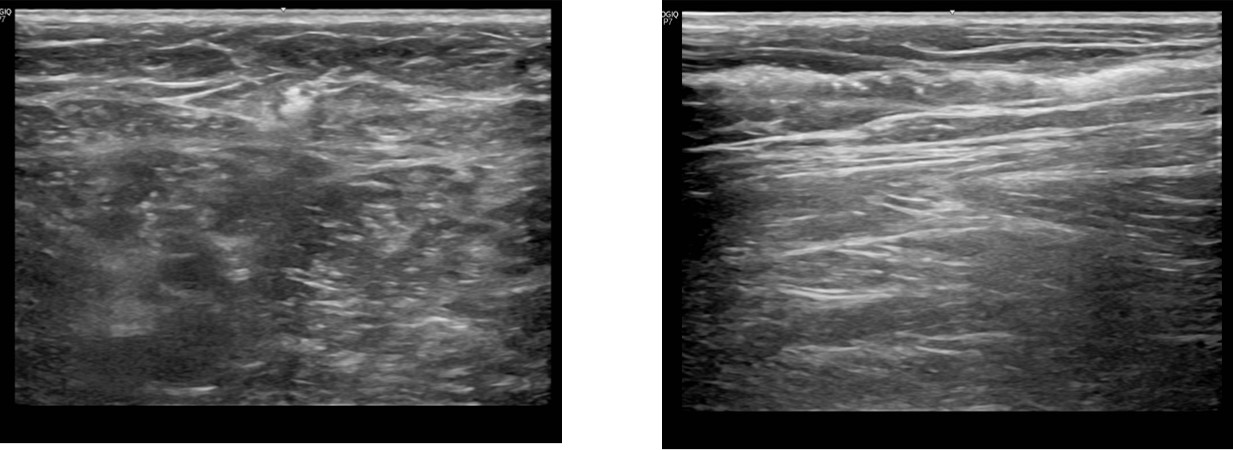

하지정맥류의 3세대치료, 비열치료의 방법으로

경피적기계화학폐쇄술

(MOCA, mechanochemical ablation)

클라리베인(ClariVein)이 현재 국내에서 사용이 되고 있습니다

최근에 이러한

의 또다른 제품으로

유럽의 폴란드에서 생산판매하는 제품으로

플레보그립 Flebogrif이라는 제품이

국내에서 허가되어 사용이 시작되었습니다